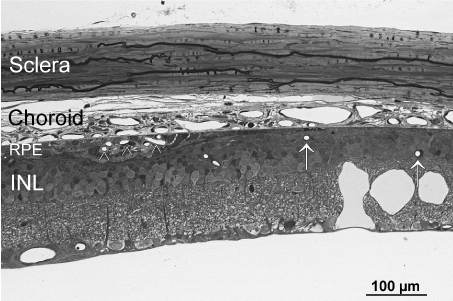

Serial semi thin sections of dystrophic RCS rat posterior eye segments revealed that all retinal neovascularizations were in close contact to the RPE with no exception (Figure 3). Areas with complete loss of RPE revealed retinal vasculature atrophy and no vessels were even close to Bruch’s membrane. The underlying choriocapillaris in these regions was degenerated, too.

Figure 3. Light microscopic overview of the retina and choroid of a 6 months old dystrophic RCS rat. Note the conglomerate of newly formed vessels in the RPE layer (arrowhead). In RPE-free regions (right side of the micrograph), retinal vessels (arrows) are all in some distance to the choroid and the constant choriocapillaries as seen on the left side are no longer present. INL=inner nuclear layer of the retina.